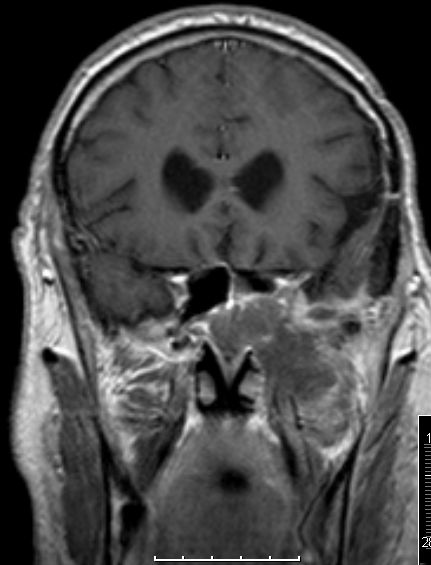

| Fall | Im vorliegenden Fall kam es während der Temodal-Therapie nach postoperativer Radiochemotherapie zu einen Durchbruch des GBs durch die Schädelbasis. | |